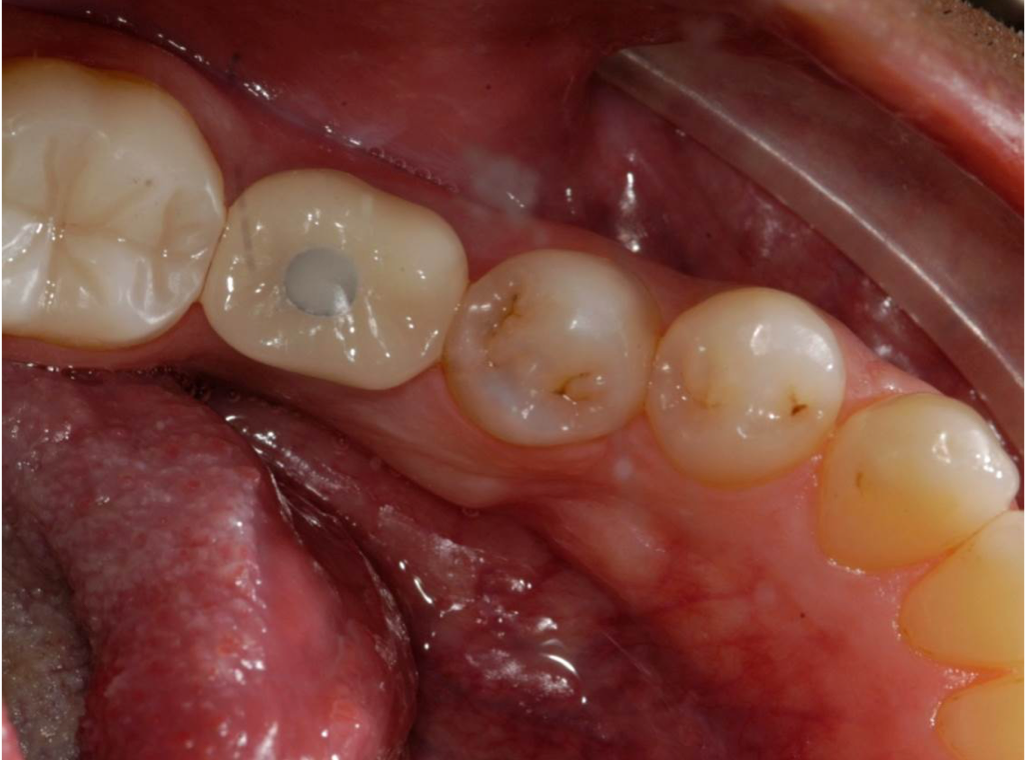

Fig 2. If the distance is less than 7 mm, an unsightly gray dot may result.

Figure 2